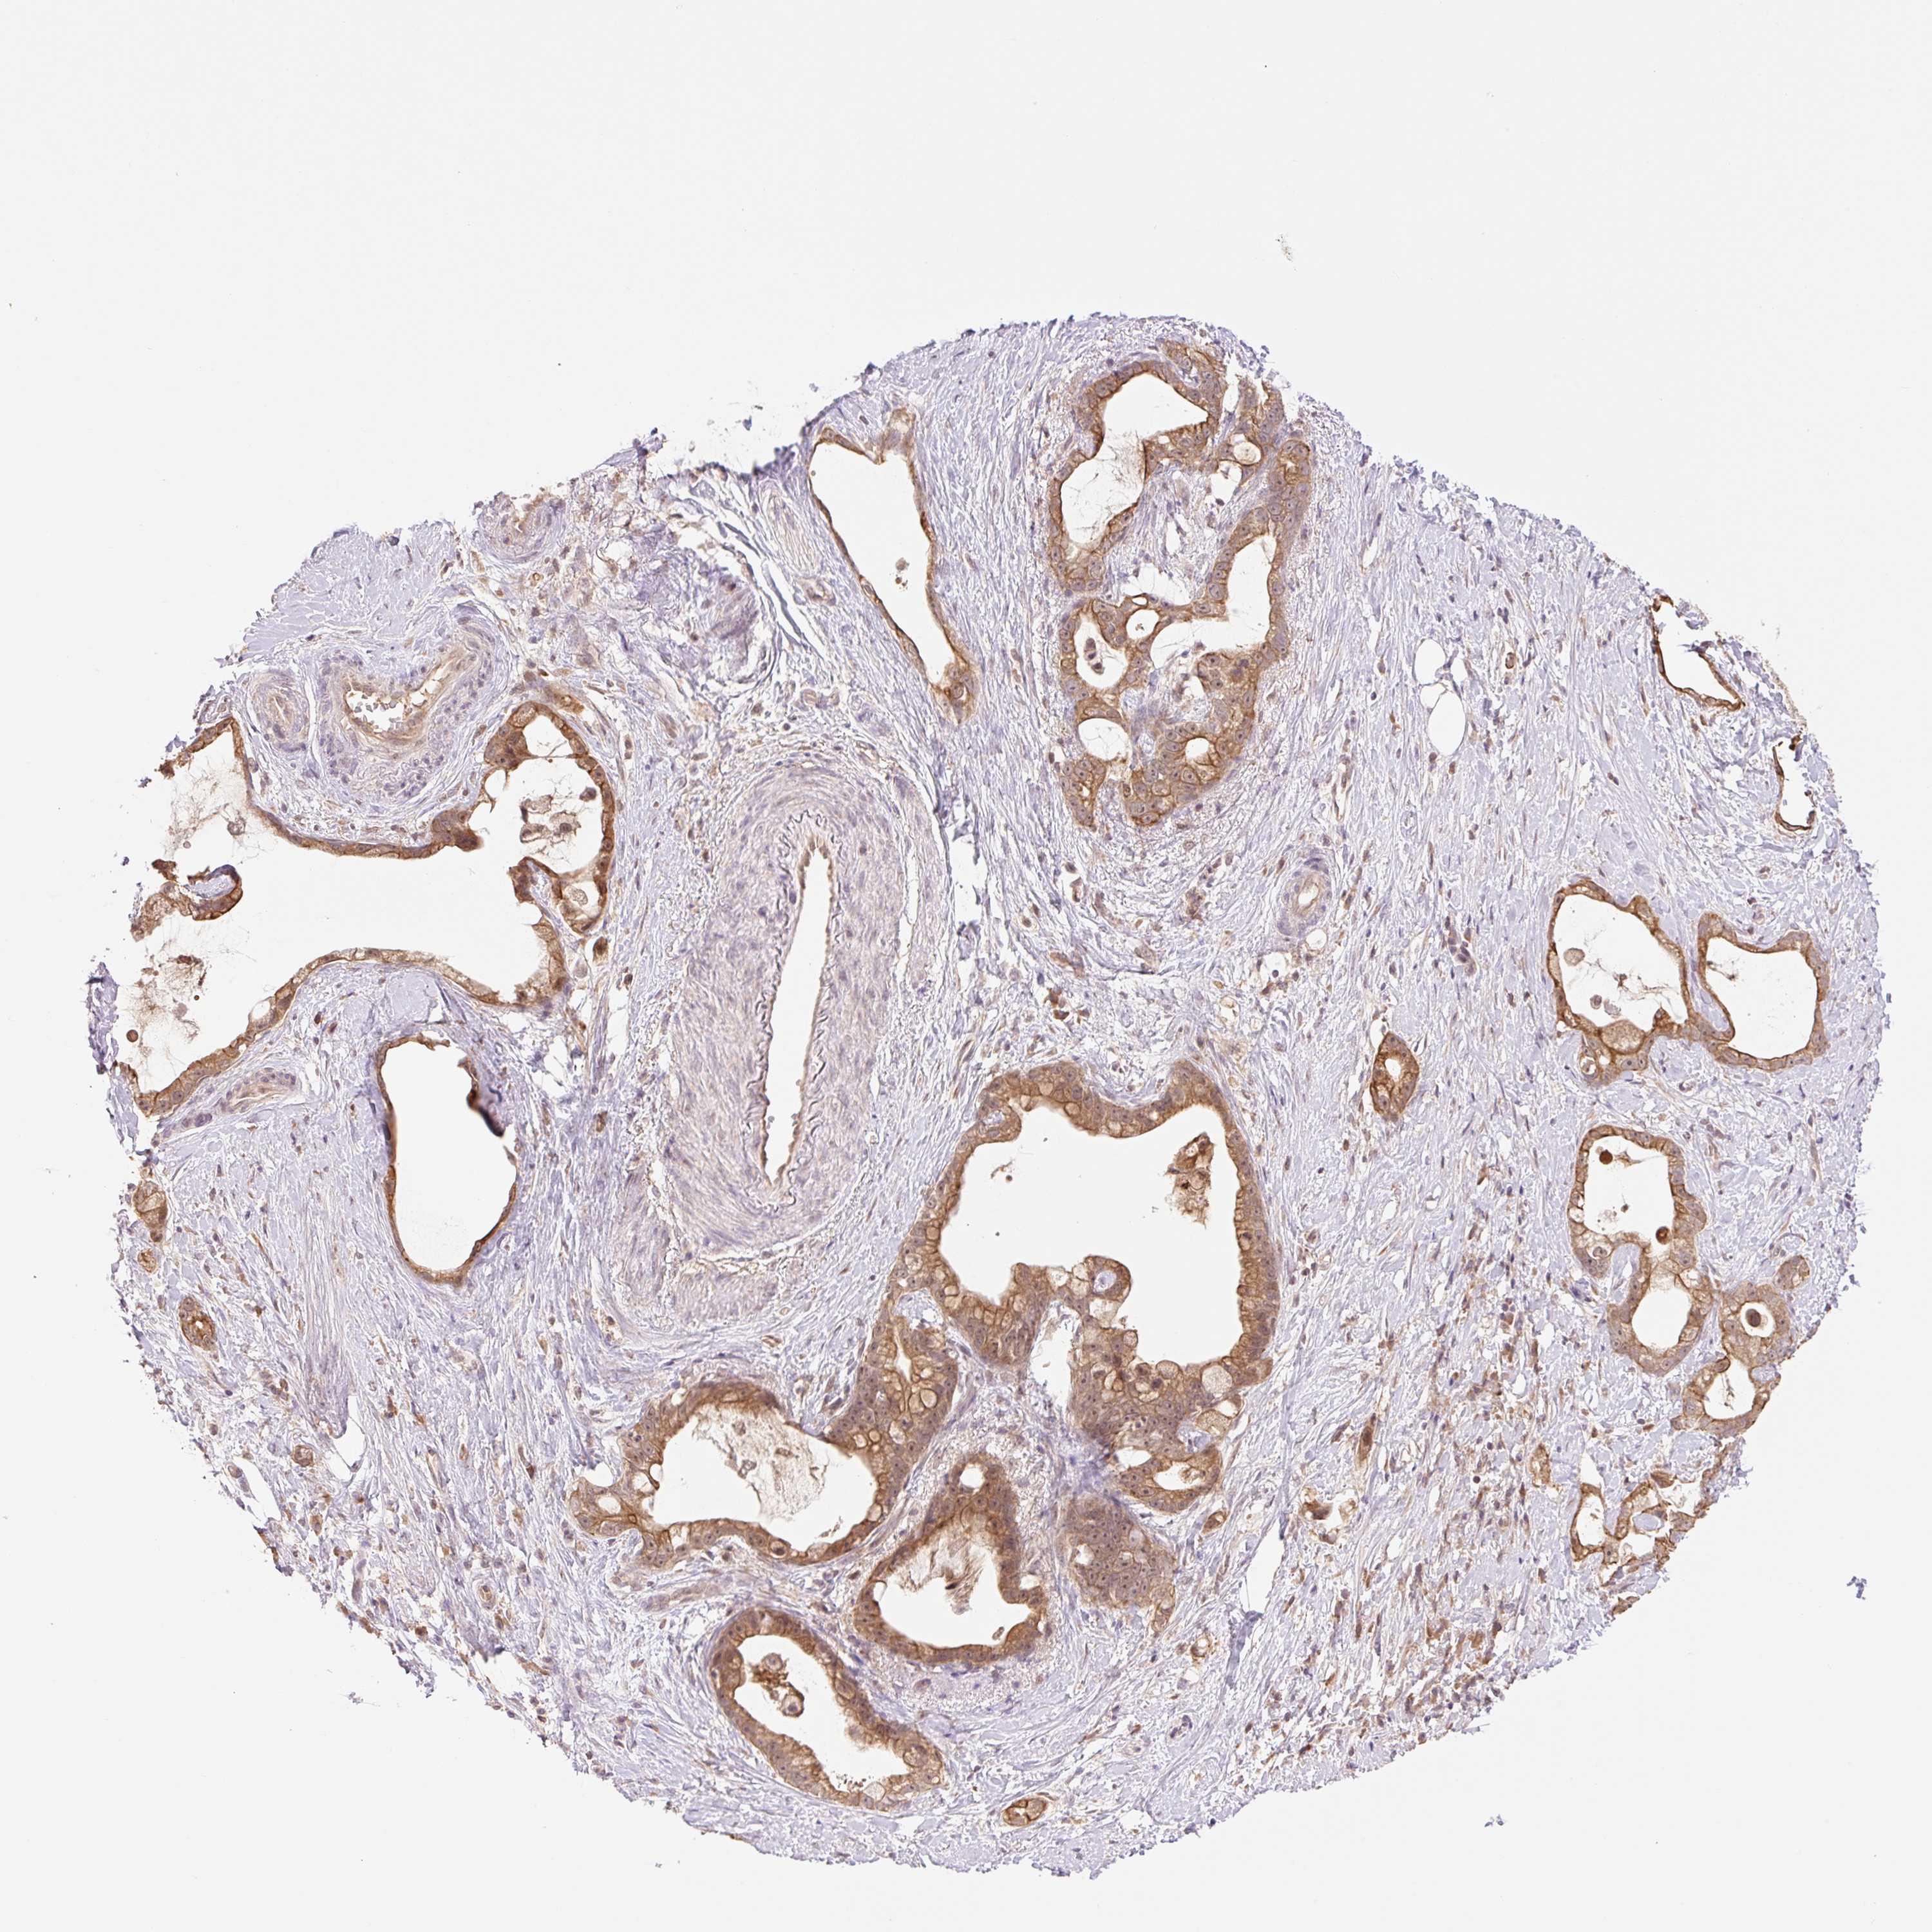

STOMACH CANCER - Protein expressioni

A mouse-over function shows sample information and annotation data. Click on an image to view it in a full screen mode. Samples can be filtered based on level of antibody staining by selecting one or several of the following categories: high, medium, low and not detected. The assay and annotation is described here.

Note that samples used for immunohistochemistry by the Human Protein Atlas do not correspond to samples in the TCGA dataset.

Antibody stainingi

Antibody staining in the annotated cell types in the current human tissue is reported as not detected, low, medium, or high, based on conventional immunohistochemistry profiling in selected tissues. This score is based on the combination of the staining intensity and fraction of stained cells.

Each image is clickable and will lead to virtual microscopy that enables deeper exploration of all samples and also displays staining intensity scores, fraction scores and subcellular localization as well as patient and tissue information for each sample.

Antibody HPA056977

Staining

High

Medium

Low

Not detected

Intensity

Strong

Moderate

Weak

Negative

Quantity

>75%

75%-25%

<25%

None

Location

Nuclear

Cytoplasmic/membranous

Cytoplasmic/membranous,nuclear

Adenocarcinoma, NOS